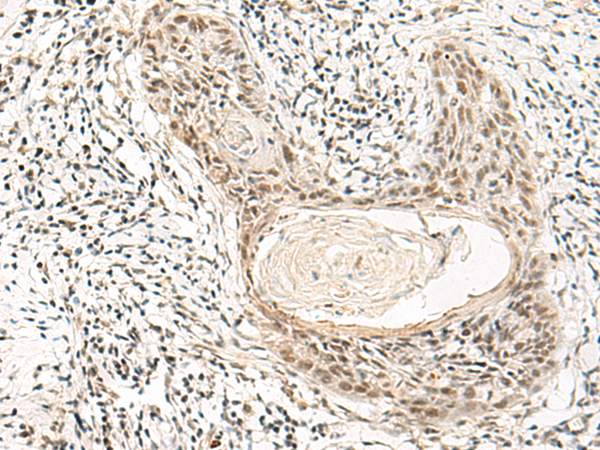

分类: 科研抗体货号: P13528别名: LGN; CMCS; PINS; DFNB82应用: IHC反应种属: Human, Mouse